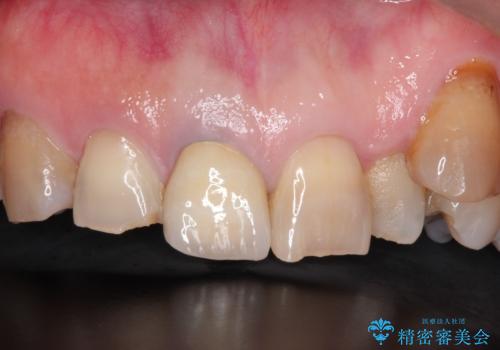

セラミックによる前歯の変色の改善

他の歯になじむ色を選択することで、自然な仕上がりにすることができました。